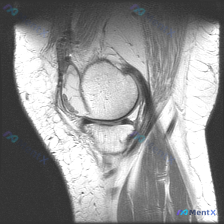

病例读片:主诉半月板异常,但这张MRI没看到明显问题?

整理了一份有意思的膝关节MRI读片病例,核心矛盾是临床提示半月板异常,但单张影像没找到对应病变,分享一下分析思路。

这是一张膝关节矢状位MRI单张切片,不是用户最初提到的肘部影像。

- 定位:膝关节矢状位,可显示股骨远端、胫骨近端、髌骨、关节间隙及相关软组织结构,解剖显示完整

- 图像质量:清晰度尚可,信噪比一般,不影响基本结构判断

- 骨性结构:骨皮质连续,无明显骨折或缺损,骨髓腔内信号均匀,无广泛水肿

- 关节间隙与软骨:关节间隙宽度正常,股骨髁、胫骨平台表面软骨显示为薄低信号带,未见明显严重软骨剥脱

- 主要韧带:髌韧带、前交叉韧带、后交叉韧带走行连续,信号均匀,未见明显断裂或异常增粗

- 软组织与关节积液:仅髌上囊及关节腔内可见少量液体信号,属于生理性范围内的轻度积液,膝关节周围软组织无明显肿胀水肿

- 髌骨:轨迹基本正常,关节间隙稳定

拿到这份资料,第一印象是:单张切片上没有看到明确的半月板急性撕裂或者明显结构性异常,核心矛盾是临床提示「半月板异常」和「影像未见明显损伤」直接冲突。